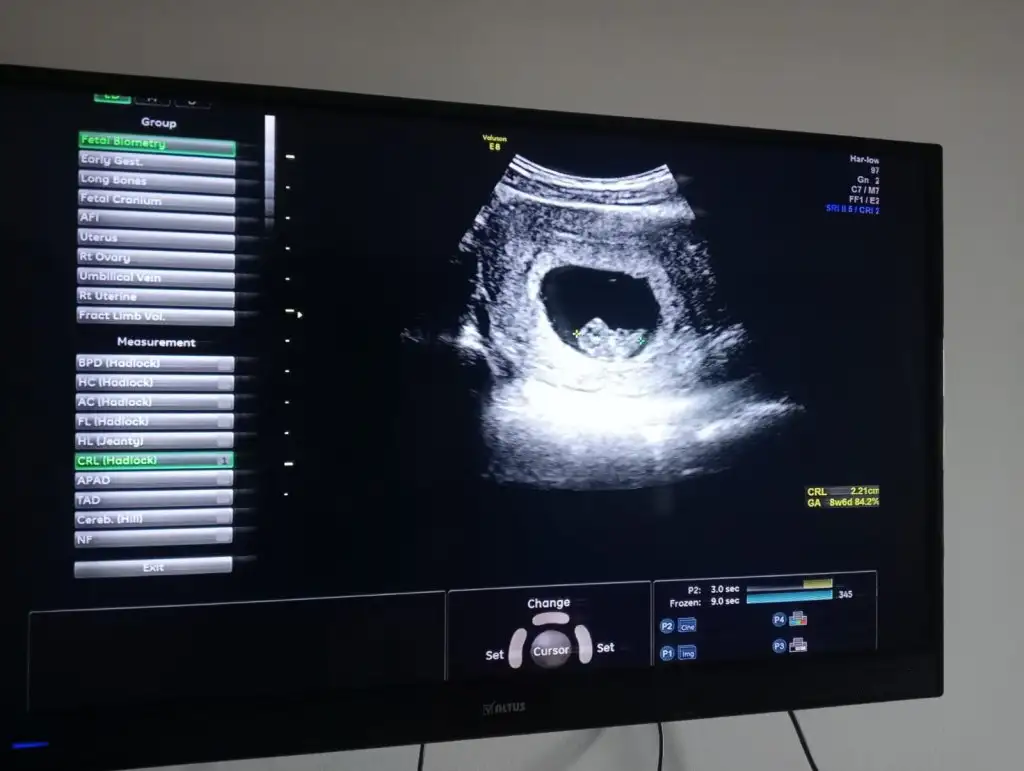

Çok sevindim hayırlı olsunBu yeni görüntümüz kızlarAllah’a şükür kalp atışını duyduk. Büyümüş dedi doktor 2 cm civarıymış. Miyomum da 7 cm olmuş düşük tehlikesi şu an için yok dedi miyomlar öyle birşey yapabiliyor çünkü Allah korusun cinsiyet tahmini yapar mısınız?